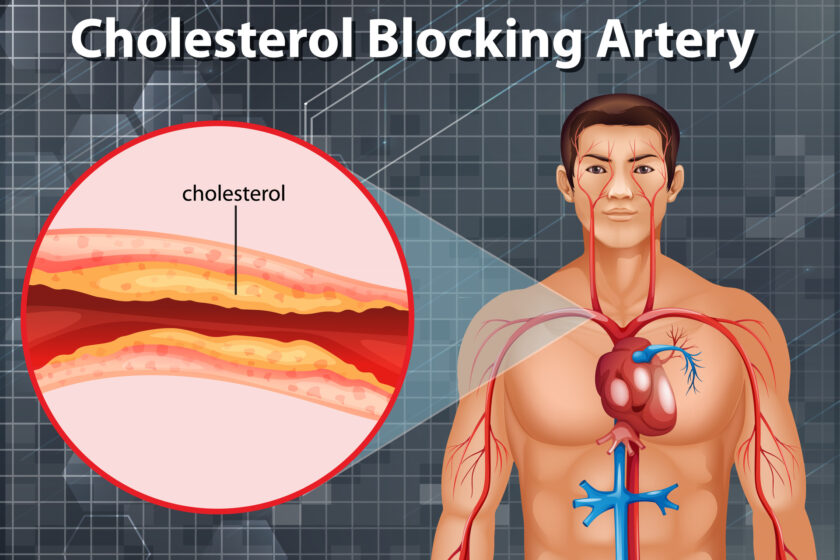

An angiogram, often referred to in common parlance as angiography, is a diagnostic procedure that utilizes sophisticated X-ray imaging to inspect blood vessels for blockages, whether they’re arteries or veins. Through this test, healthcare professionals can closely observe blood circulation at specific points within the body, helping them identify the source of an arterial or venous issue.

The need for an angiogram arises when there are indications of damaged, blocked, or abnormal blood vessels. This test facilitates healthcare providers in ascertaining the root cause of the vascular problem and understanding the extent of damage to the vessels.

Some common reasons why an angiogram is done include diagnosing or planning treatment for:

- Coronary artery disease.

- Peripheral artery disease.

- Atherosclerosis.

- Blood clots.